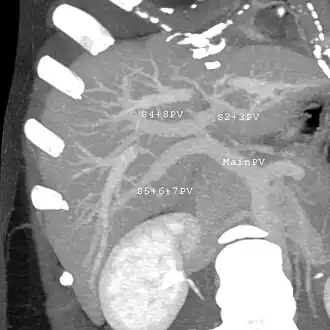

A CT scan in which the liver and portal vein are shown

With the recent advances of noninvasive imaging, living liver donors usually have to undergo imaging examinations for liver anatomy to decide if the anatomy is feasible for donation. The evaluation is usually performed by multidetector row computed tomography (MDCT) and magnetic resonance imaging (MRI). MDCT is good in vascular anatomy and volumetry. MRI is used for biliary tree anatomy. Donors with very unusual vascular anatomy, which makes them unsuitable for donation, could be screened out to avoid unnecessary operations.

-

MDCT image. Arterial anatomy contraindicated for liver donation -

MDCT image. Portal venous anatomy contraindicated for liver donation -

MDCT image. 3D image created by MDCT can clearly visualize the liver, measure the liver volume, and plan the dissection plane to facilitate the liver transplantation procedure. -

Phase contrast CT image. Contrast is perfusing the right liver but not the left due to a left portal vein thrombus.